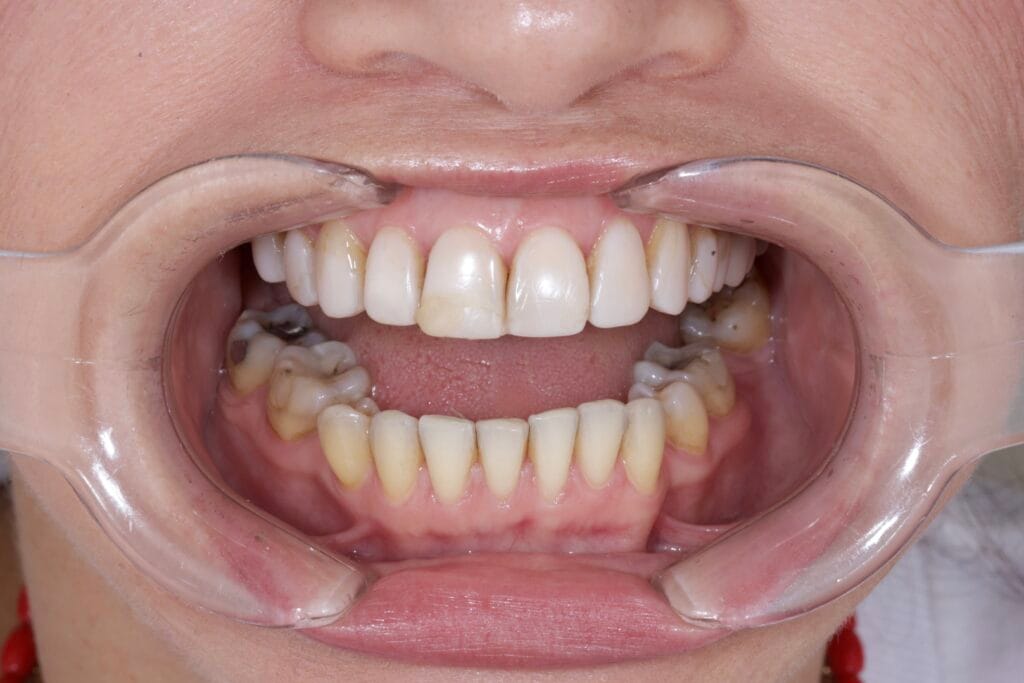

Our patient arrived with an existing resin smile design that no longer met her expectations. Over time, the restorations became completely disadapted and compromised both aesthetics and function. As a result, margins deteriorated, proportions lost balance, and the smile stopped integrating harmoniously with her facial features.

Additionally, we faced a significant challenge: a deviated dental midline. Therefore, this case required a precise and thoughtful approach guided by facial analysis in smile design.

Through photographic analysis, digital planning, and direct patient evaluation, we can decide whether to correct, soften, or visually disguise a midline deviation.